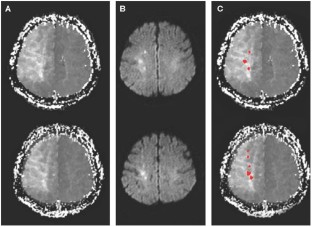

Chaves CJ et al. (2000) Diffusion- and perfusion-weighted MRI patterns in borderzone infarcts. Stroke 31: 1090–109649

Wiart M et al. (2000) Vasodilatory response of border zones to acetazolamide before and after endarterectomy: an echo planar imaging-dynamic susceptibility contrast-enhanced MRI study in patients with high-grade unilateral internal carotid artery stenosis. Stroke 31: 1561–1565

Bisschops RH et al. (2003) Association between impaired carbon dioxide reactivity and ischemic lesions in arterial border zone territories in patients with unilateral internal carotid artery occlusion. Arch Neurol 60: 229–233